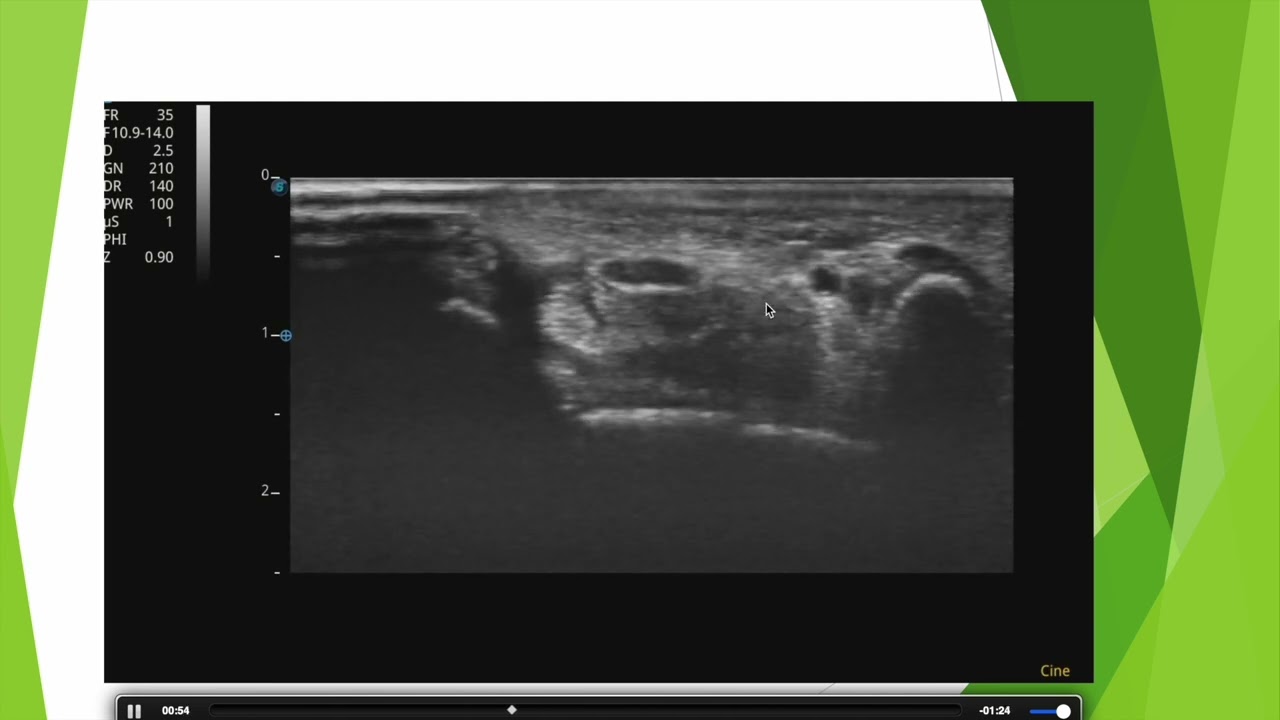

Repérer facilement le nerf médian en échographie au niveau du canal carpien

Avec ma technique de l'ascenseur vous n'aurez jamais plus aucune difficulté pour repérer le nerf médian au niveau du poignet.